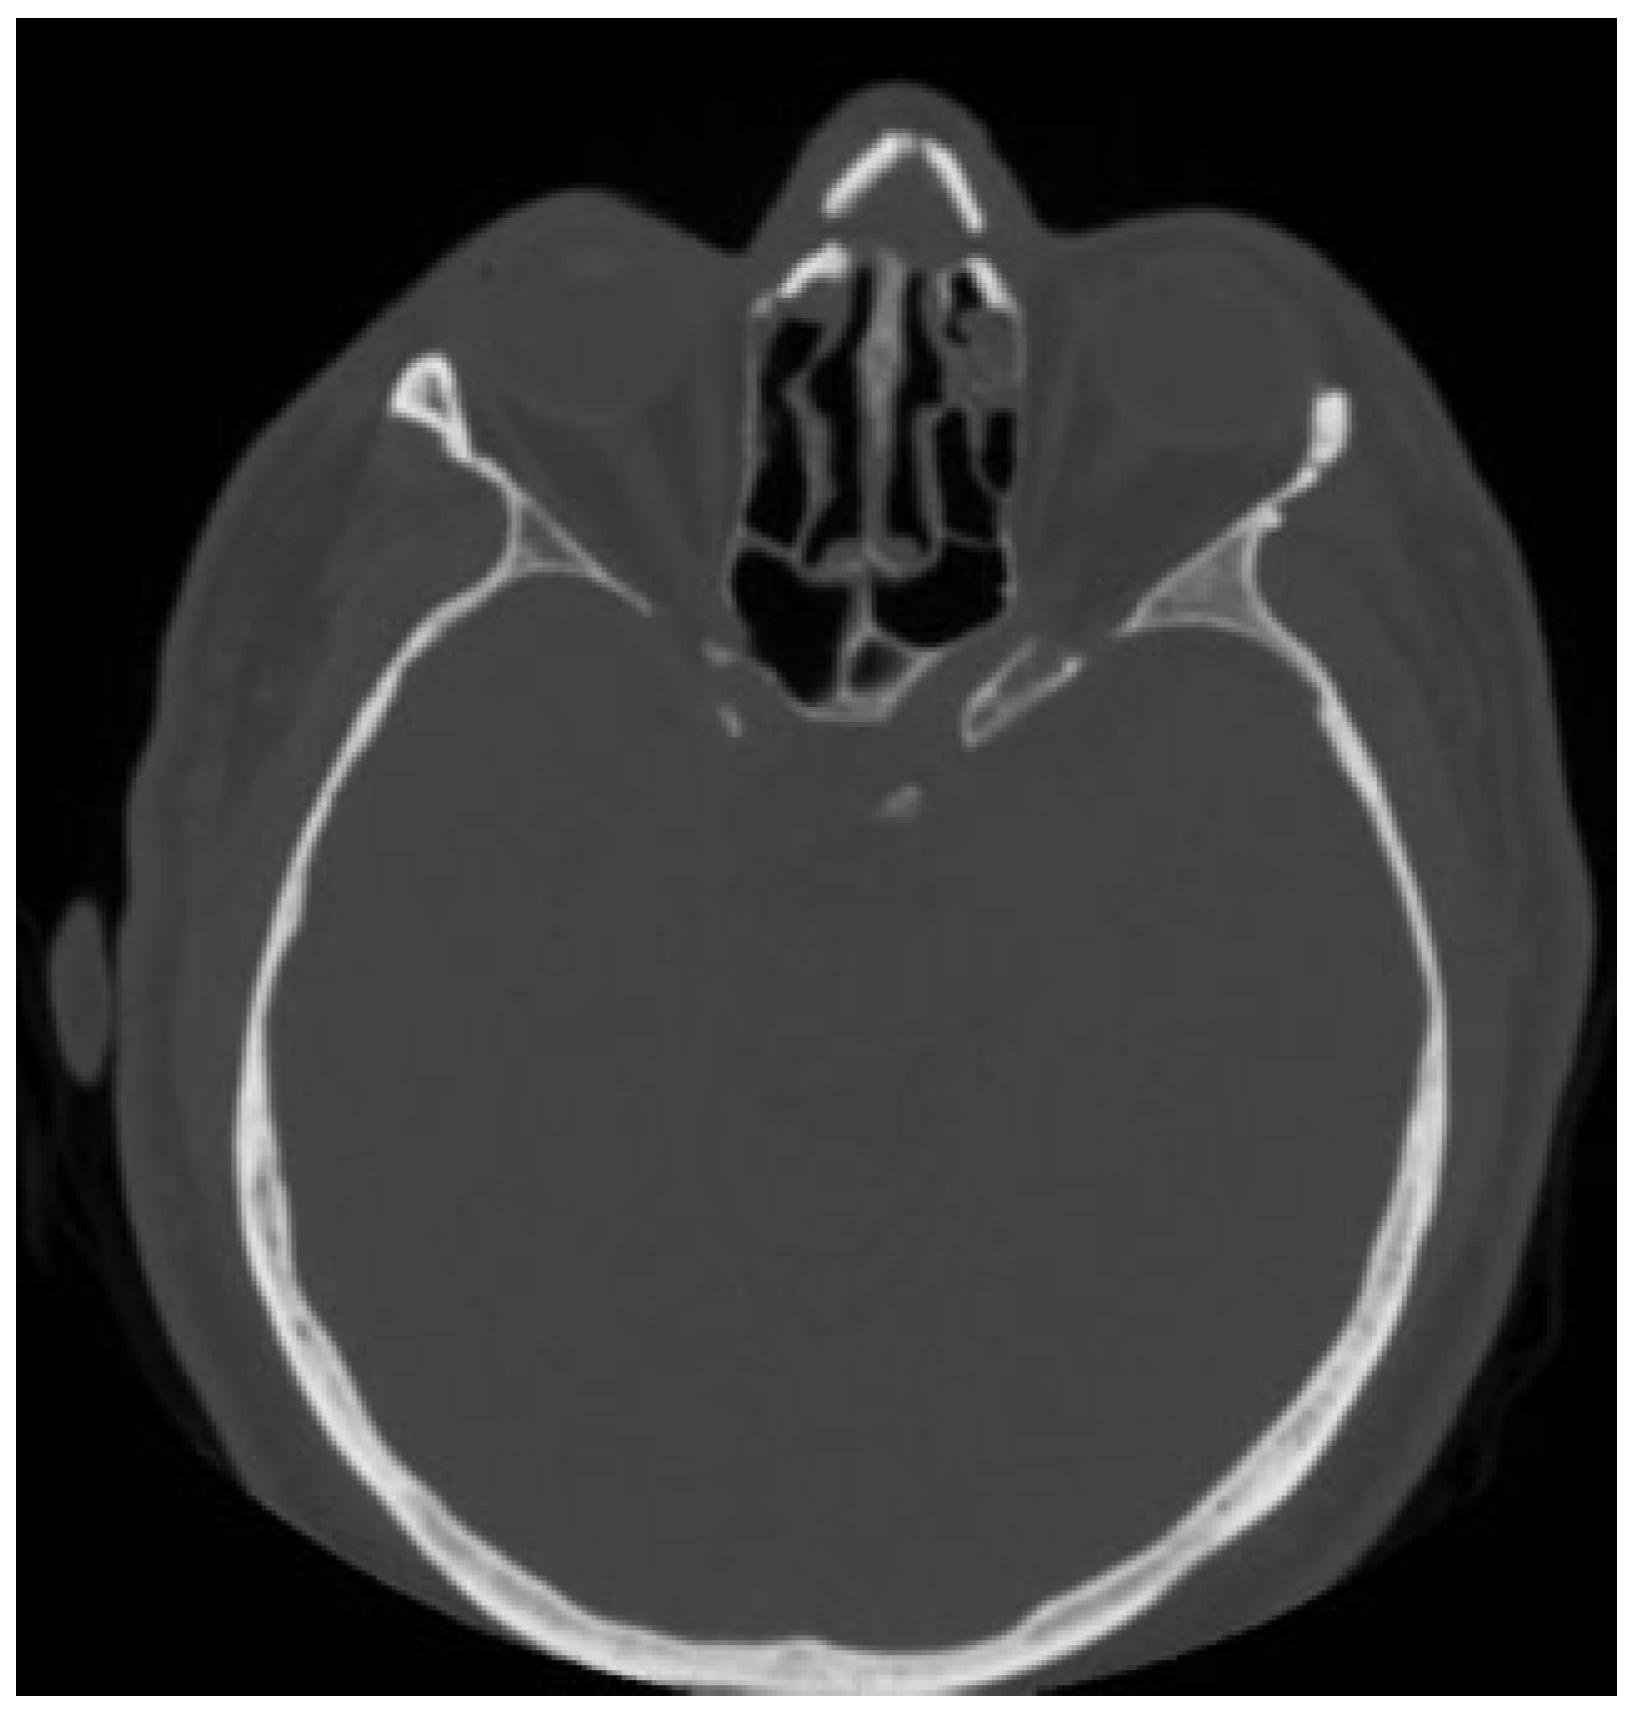

The recovery was uneventful. A 2-month postoperative CT scan showed good reconstruction of the nose and the glabellar area and frontal sinus patency with a minimal mucosal thickening of the frontoethmoidal recess (Figure 8 and Figure 9). No late complications occurred, appearance of the face returned to normal, and the results were stable at 12-month follow-up with the patient’s full satisfaction with his facial appearance (Figure 10).

Figure 9. Postoperative CT scan showing frontal sinus patency with a minimal mucosal thickening of frontoethmoidal recess.